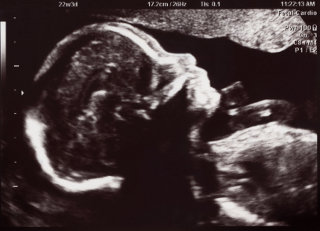

Their petition to the Court of Session in Edinburgh stated: "They hold a religious belief that all human life is sacred from the moment of conception and that termination of pregnancy is a grave offence against human life."